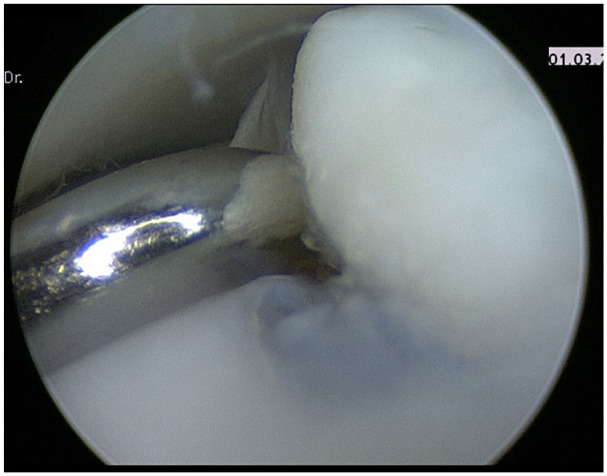

Abstract Image